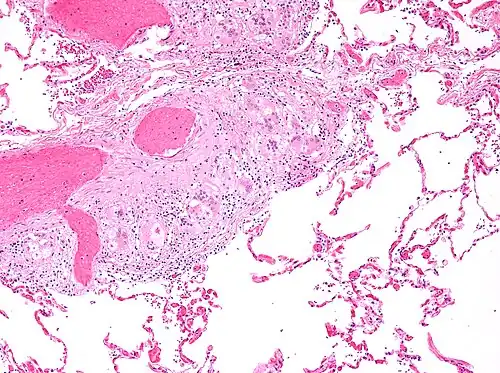

Histopathology

Sarcoidosis is characterized by the formation of non-necrotizing ("non-caseating") granulomas in various organs and tissues.[95] Giant cells, specifically Langhans giant cells, are often seen in sarcoidosis.[96] Schaumann bodies seen in sarcoidosis are calcium and protein inclusions inside of giant cells as part of a granuloma.[97] Asteroid bodies can be seen in sarcoidosis.[97] Hamazaki–Wesenberg bodies can be seen in lymph nodes and more rarely in lung biopsies with sarcoidosis and are inclusion bodies of lysosomes with protein, glycoprotein and iron.[98]